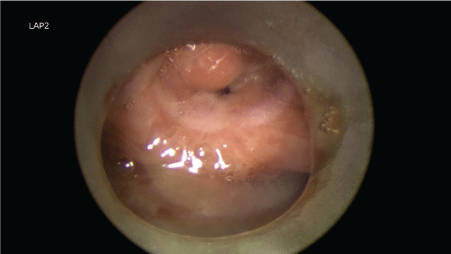

Flexible laryngoscopy revealed a mass at right false cord extending to left false cord. Both vocal cords were not clearly visualized. Initially tumour was staged as T2N1MO, with suspicion of reactive lymph node. Airway was only about 25%, almost closing on inspiration; hence, tracheostomy was performed and preceded with direct laryngoscopy. A friable mass was seen over left false cord, extending into anterior commissure and right vocal cord at its anterior one third. The mass also seen extending anteriorly into the subglottic area 1.5 cm below the vocal cords (Figure 1). Esophagocopy was normal. First biopsy taken in August 2015 showed severe dysplasia with area suspicious of invasion. It was suggested by the pathologist for deeper biopsy. Subsequently, CT imaging showed findings of a laryngeal tumour, involving both false and true cords, with transglottic extension, and invasion into pre-epiglottic and both paraglottic spaces. But no distant metastasis has been reported (Figure 2). Based on the CT findings, the tumour was staged as T4N1M0. A second biopsy done in October 2015 showed more extensive mass involving both true cords and false cords. The mass also involved both the anterior and posterior commisures. The delay in second biopsy was because patient went to a different hospital for second opinion. The second biopsy confirmed moderately-differentiated squamous cell carcinoma. The tumour was already more extensive from initial staging of T2N1M0 to a T4N1M0 transglottic tumour. Meanwhile tissue sent for AFB culture and smear also confirmed laryngeal tuberculosis.